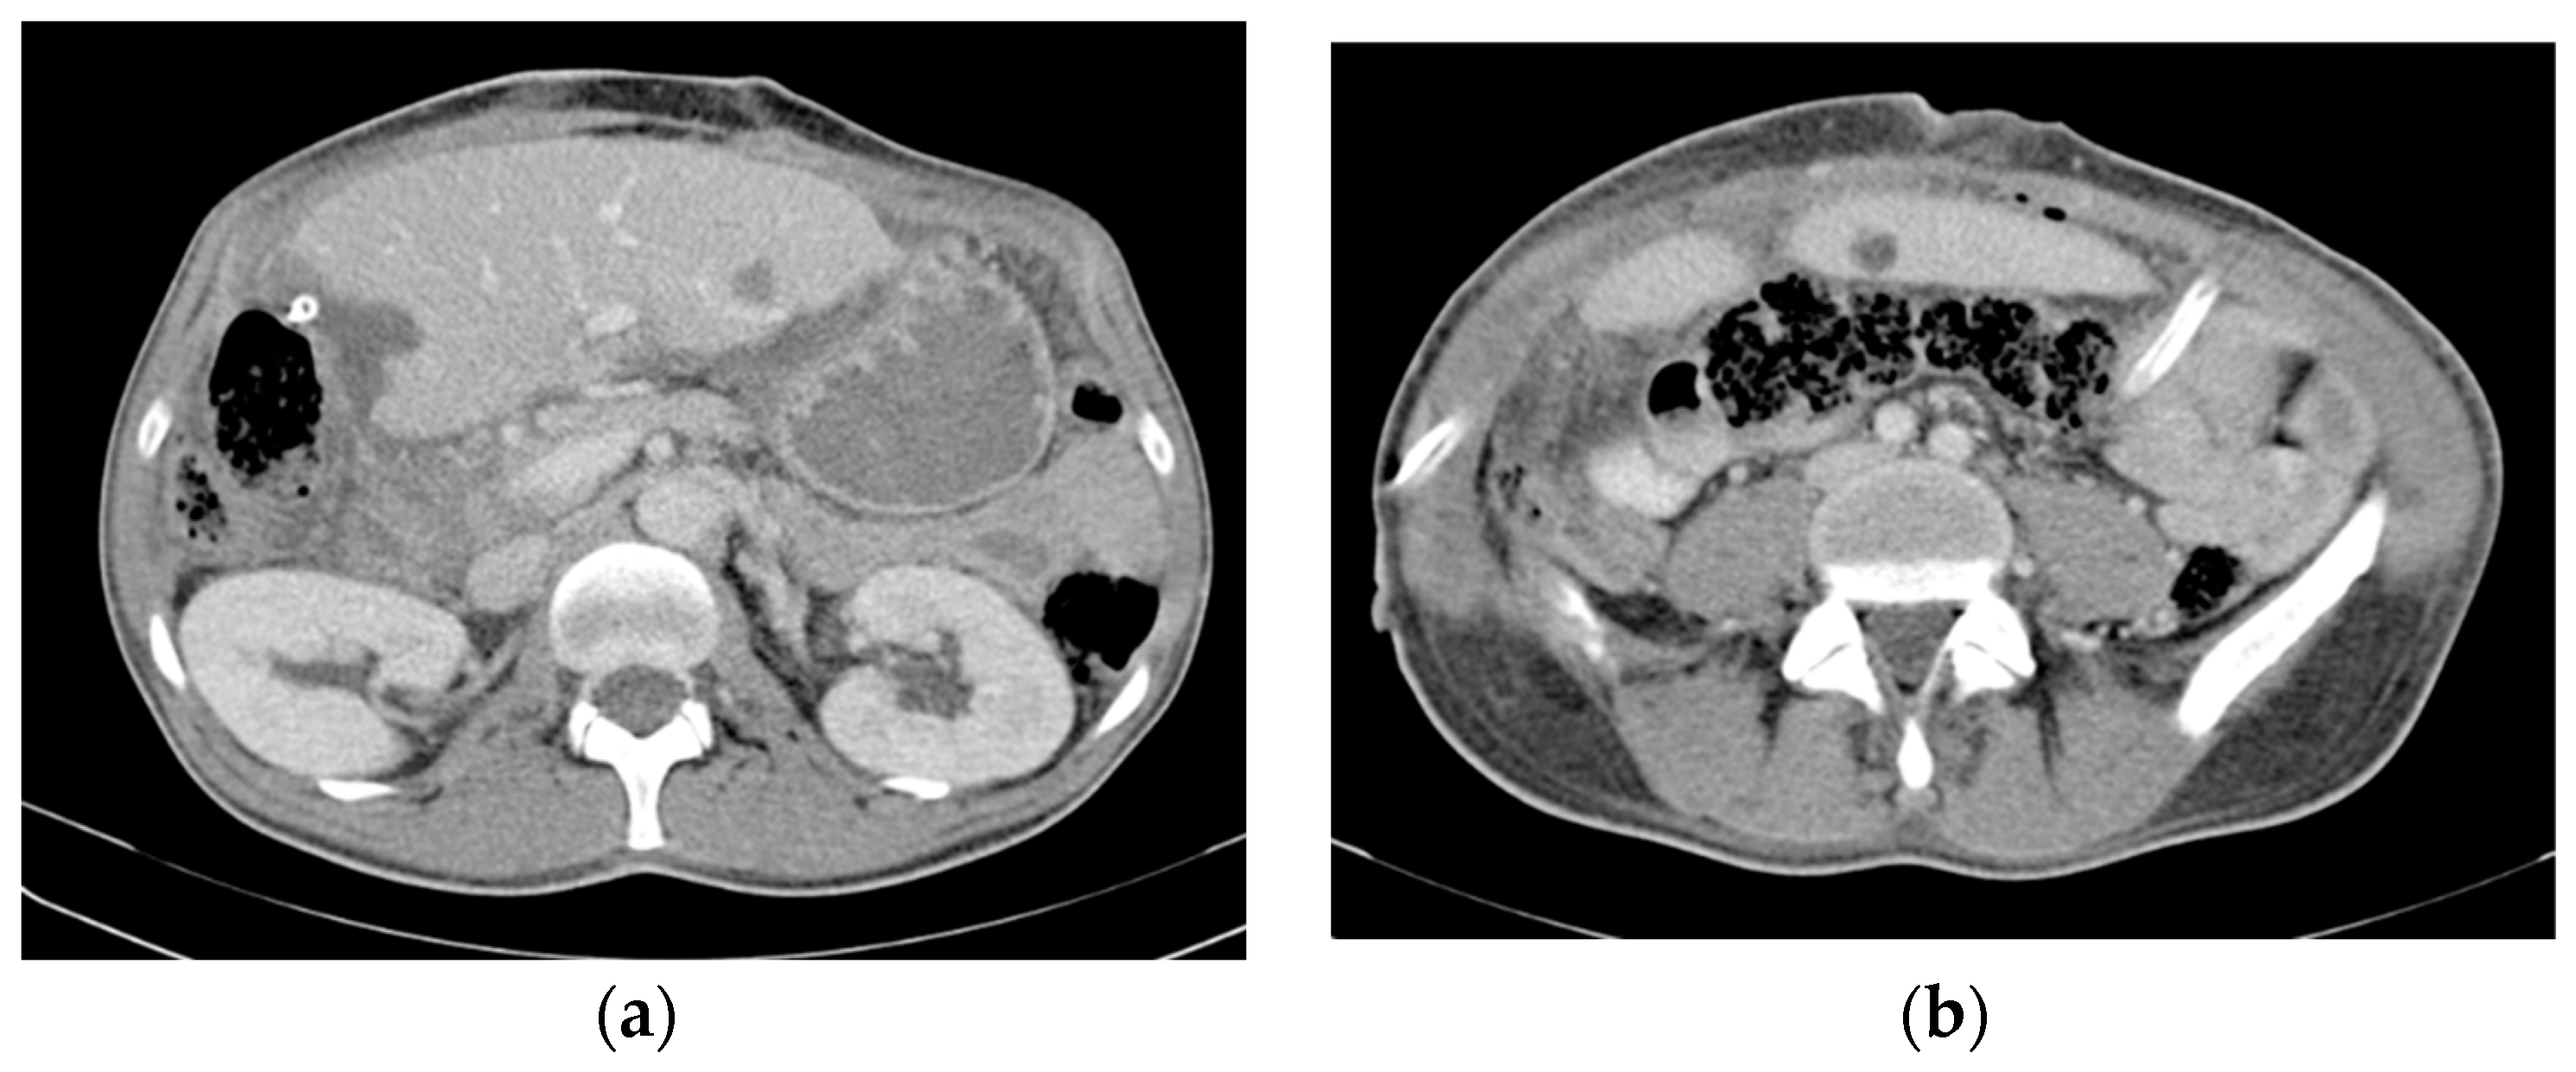

The operative time was 480 min, and blood loss was 2700 mL, necessitating a five-unit blood transfusion. The postoperative course was relatively uneventful, with the exception of fever on POD 11 (remitted by antibiotherapy) and right pleural effusion requiring drainage on POD 12. The patient was discharged on POD 19. The CT scan performed before discharge showed few remaining small liver metastases (the largest had a diameter of 26 mm) and asymptomatic small fluid accumulation on the liver cut surface (treated conservatively) (Figure 7).

Figure 7.

Contrast-enhanced postresection CT image showing (a) a few remaining small liver metastases (the largest of which had a diameter of 26/17 mm) (b) and an asymptomatic collection on the liver resection surface.